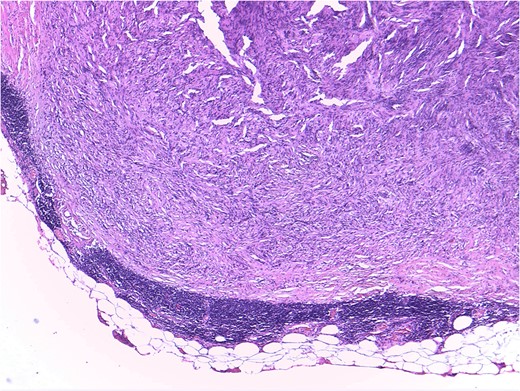

Mesenteric node tumor microscopically constituted by a spindle cell proliferation without atypia, mitosis or necrosis, displacing the normal limphatic tissue toward periphery.